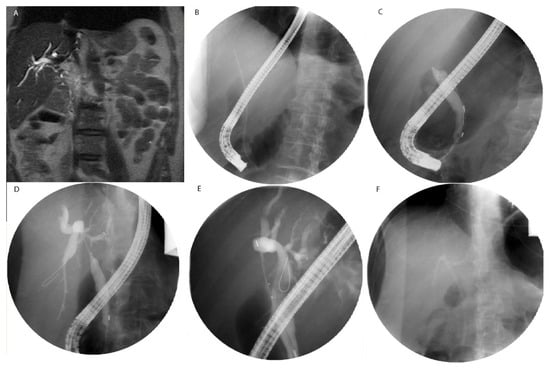

10.2. Photodynamic Therapy in Non-HCC Primary Liver Malignancy

10.3. Photodynamic Therapy in Metastatic Disease to the Liver